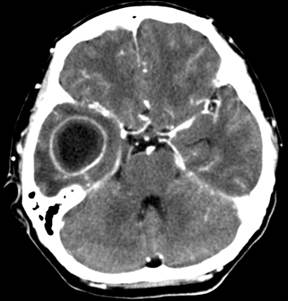

8. Topic: Central Nervous System Infections

Subtopic: Meningitis

Non-Clinical Question:

A 39-year-old patient with HIV and a CD4 count of 139 cells/uL presents with altered sensorium and impaired consciousness. CSF examination using an India ink preparation reveals a positive result. Which organism is most likely responsible? (Microbiology)

33. Topic: Ear

Subtopic: Otitis Media

Clinical Question:

2. A patient with CSOM presented to the OPD with seizures, headache and complaints of nausea and vomiting. CT image of patient is given. Identify the clinical condition? (ENT)

Options:

- Temporal abscess

- Extradural abscess

- Meningitis

- Petrositis

Correct Answer: A) Temporal abscess